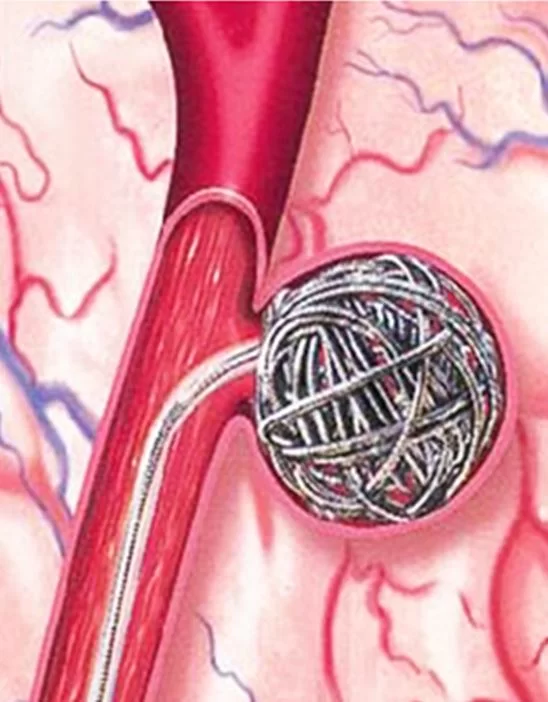

Στην περίπτωση του εμβολισμού (με τον οποίο αντιμετωπίζονται πλέον περίπου το 70% των ανευρυσμάτων), προωθείται ένας καθετήρας μέχρι το ανεύρυσμα και στη συνέχεια το ανεύρυσμα «γεμίζει» με μικρά ελάσματα (πολύ μικρά σύρματα) και έτσι αποκόπτεται από την κυκλοφορία (Εικόνα 3).